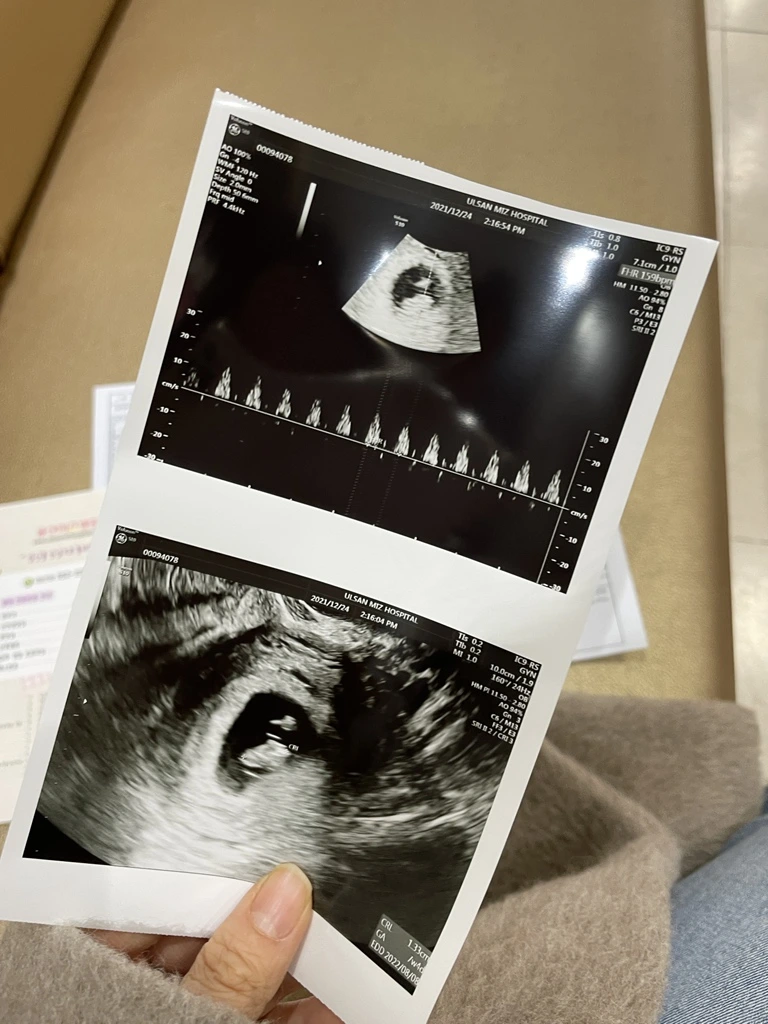

아기집에 아무것도 안보여 걱정했지만 다음주 아기와 심장소리까지!